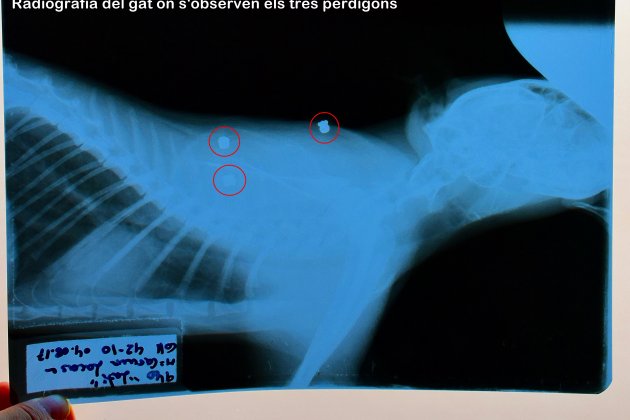

La propietària manifesta que "no és la primera vegada que ho fa" i, de fet, la denúncia recull que en els dos últims anys han mort una desena de gats per trets o enverinats i en tots els casos se sospita que el responsable n'és la mateixa persona. Les denúncies anteriors no van tirar endavant per falta de proves. En aquest cas, a la denúncia s’hi ha incorporat l’informe veterinari que constata que el gat tenia tres perdigons en diferents parts del cos.